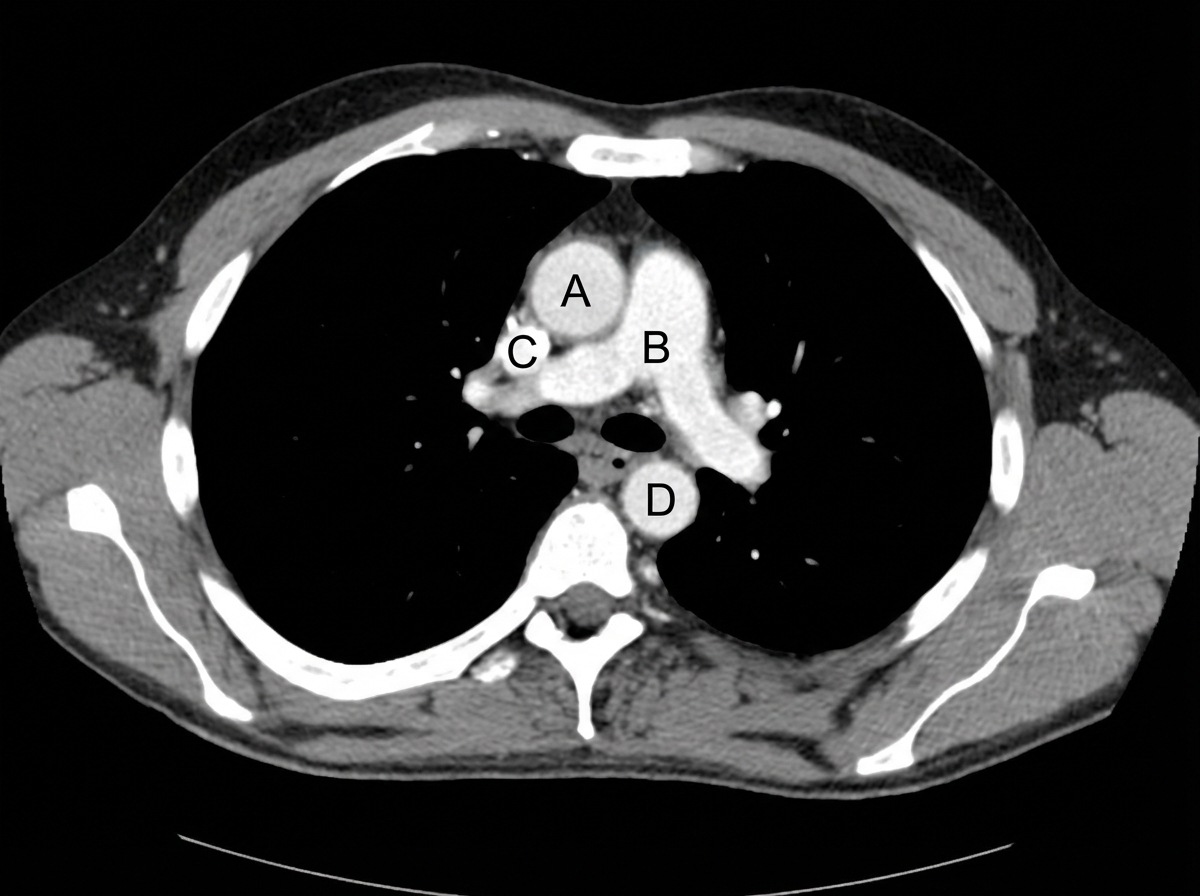

Identify the labeled structures correctly in the axial CT image of the thorax

Explanation: ***A - Ascending aorta, B - Pulmonary trunk, C - Superior vena cava, D - Descending aorta*** - **A** points to the **ascending aorta**, which is the large artery arising from the left ventricle and supplying oxygenated blood to the systemic circulation. On this axial view, it is typically located anterior and to the right of the pulmonary artery. - **B** points to the **pulmonary trunk**, which emerges from the right ventricle and bifurcates into the pulmonary arteries to carry deoxygenated blood to the lungs. It is positioned anterior and to the left of the ascending aorta at this level. - **C** points to the **superior vena cava**, a large vein that collects deoxygenated blood from the upper half of the body and drains into the right atrium. It is typically located to the right and slightly posterior to the ascending aorta at this level. - **D** points to the **descending aorta**, which continues from the aortic arch downwards through the chest and abdomen to supply blood to the lower body. It is visible posteriorly and to the left of the vertebral body on this axial CT image. *A - Pulmonary trunk, B - Ascending aorta, C - Superior vena cava, D - Descending aorta* - This option incorrectly identifies A as the pulmonary trunk and B as the ascending aorta; the **ascending aorta** is typically positioned more anteriorly and to the right compared to the **pulmonary trunk** at this level. - The relative positions of the pulmonary trunk and ascending aorta are swapped, leading to an incorrect labeling. *A - Superior vena cava, B - Pulmonary trunk, C - Ascending aorta, D - Descending aorta* - This option incorrectly identifies A as the superior vena cava and C as the ascending aorta. The **superior vena cava** is typically located to the right of the ascending aorta, not anterior-central. - The **ascending aorta** is usually the most anterior and central great vessel in the mediastinum at this level, which does not correspond to C. *A - Ascending aorta, B - Superior vena cava, C - Pulmonary trunk, D - Descending aorta* - This option incorrectly identifies B as the superior vena cava and C as the pulmonary trunk. **Superior vena cava** is a venous structure and is not typically located in the position of B, which is an arterial structure (pulmonary trunk). - The **pulmonary trunk** is usually more anterior and central than the position of C, which correctly identifies the superior vena cava in other options.